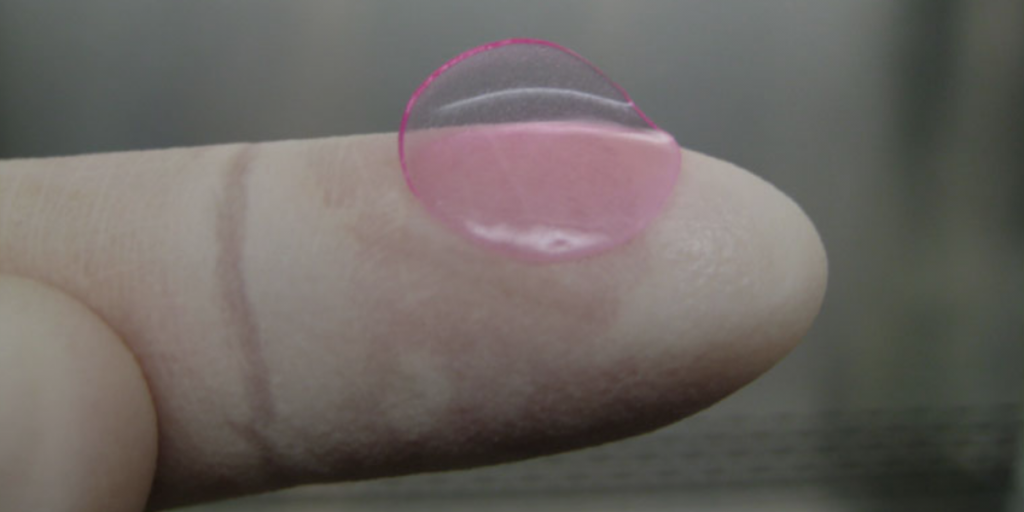

| MACI | Vericel Corporation | MACI® (Condrócitos Autólogos Cultivados em Membrana de Colágeno Porcino) é um produto de estrutura celular destinado ao reparo de defeitos sintomáticos únicos ou múltiplos da cartilagem do joelho com ou sem envolvimento ósseo em adultos. |